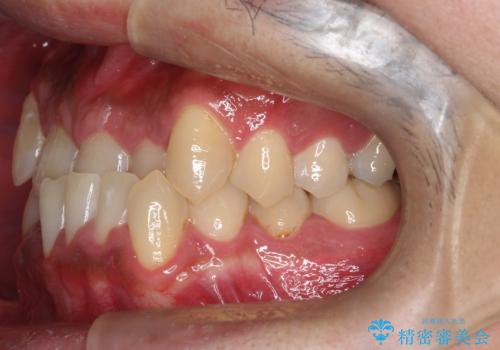

- 主訴:噛み合わせが反対になっているのを治したい

反対咬合と叢生改善のため、上下左右4番目の歯を抜歯し、審美装置にて矯正治療を行いました。

骨格性Ⅲ級を示しましたが、構成咬合位がとれたことから反対咬合と叢生改善のため、上下左右第一小臼歯を抜歯しワイヤー矯正を行いました。途中、バイトアップを行っています。